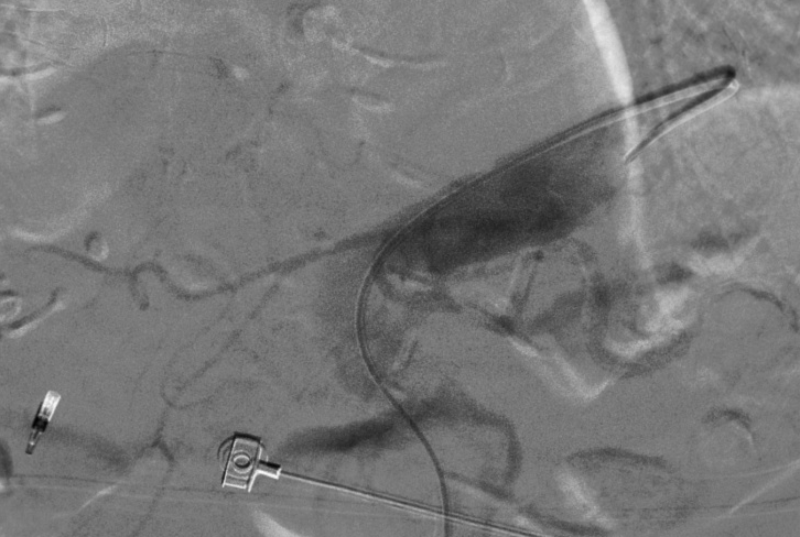

造影顯示肝總動脈發出胃十二動脈及肝左右動脈。但胃十二指腸多處彎曲,微導管進入胃十二指腸動脈遠端困難,更換成超細導絲后最后將微導管送入胃十二指腸動脈遠端。

經微導管注入栓塞劑到胃十二指腸動脈全程,造影顯示胃十二指腸動脈栓塞徹底,肝內動脈分支血運良好無副栓塞。